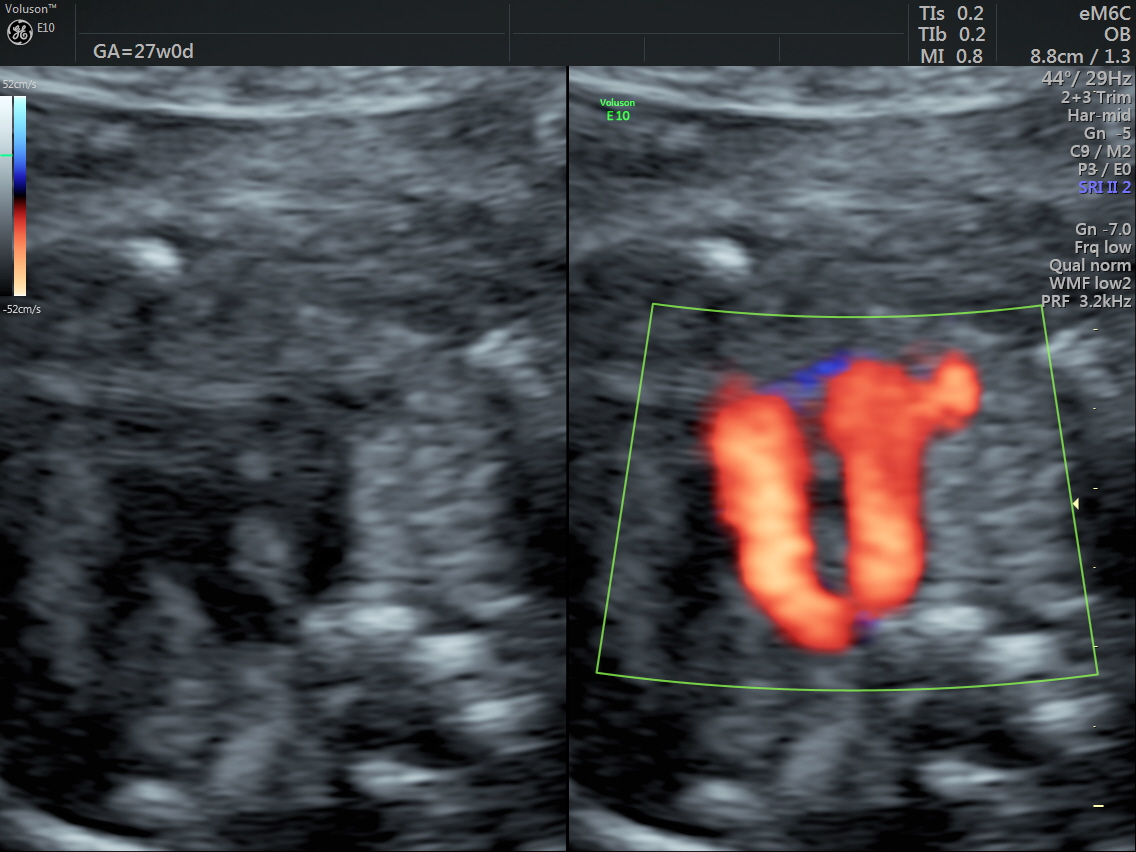

RT AORTIC ARCH_22 Published June 17, 2016 at 1136 × 852 in Rt aortic arch and aberrant left subclavian artery ← Previous Next →